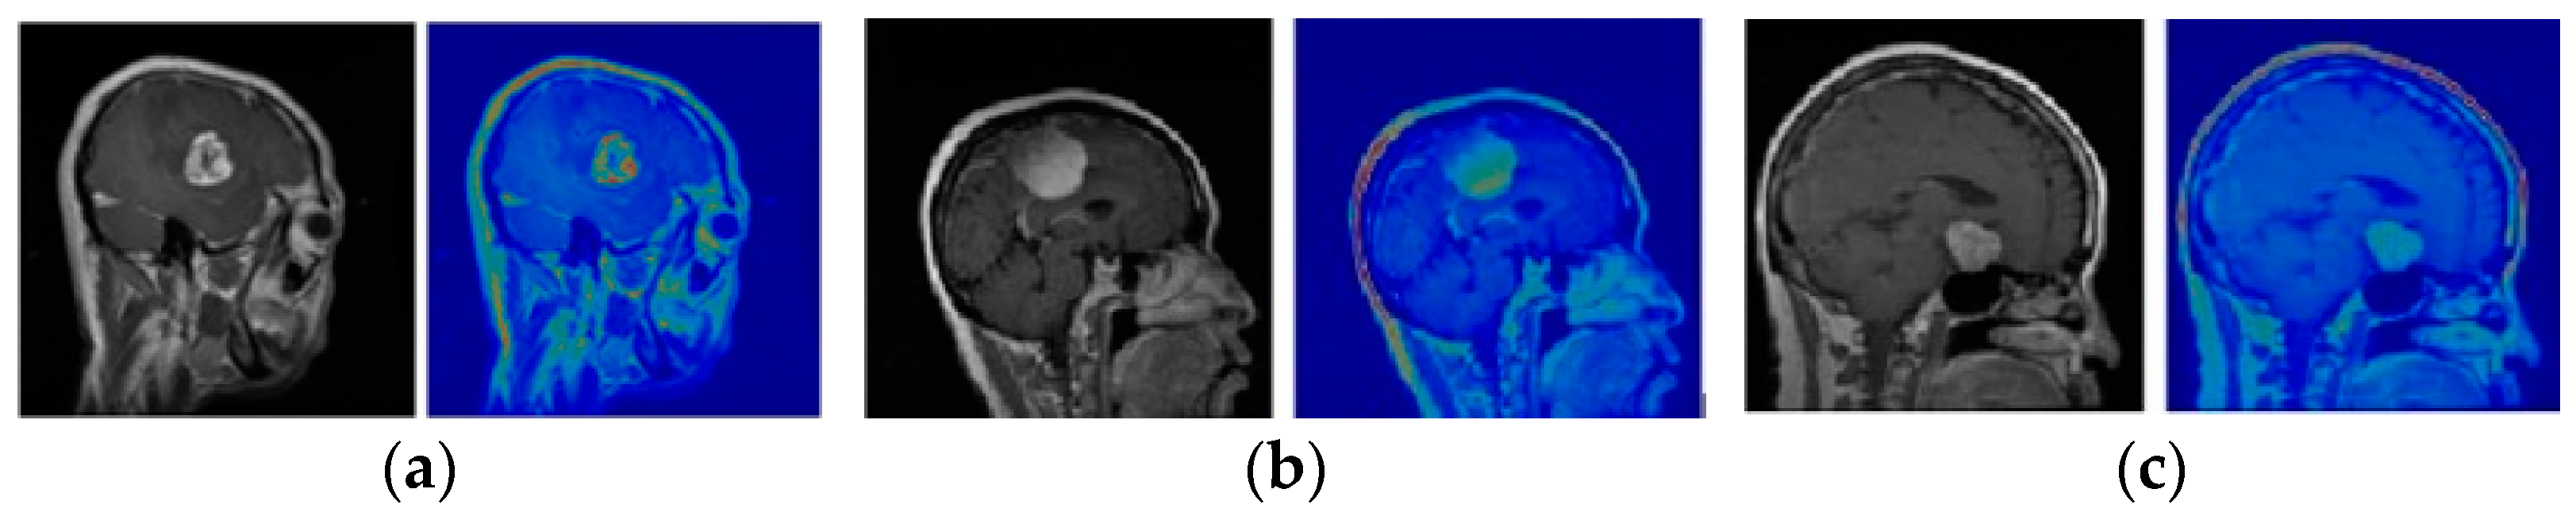

The paper employed the Brain Tumor MRI Dataset from Kaggle, encompassing 7023 images, with 4117 utilized for CNN training including glioma (1321), meningioma (1339), and pituitary tumors (1457). These grayscale images with intensity values ranging from 0 to 255 depict cancerous tumors. Assessing real effectiveness may differ between training databases and real-world studies due to variations in tumor structures and other factors [14]. Figure 1 show examples of tumors.

Figure 1. RM images of a glioma on the left, meningioma in the center, and pituitary on the right.